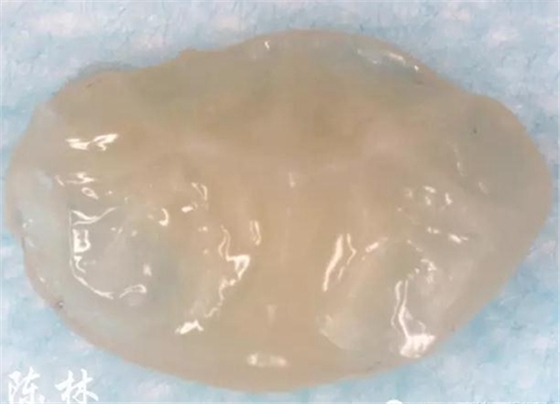

(圖3)制作樹脂印章:樹脂材料按壓于36咬合面,光照;注意牙面不要涂布粘接劑

(圖4)樹脂印章的舌面觀:復制合面的解剖外形